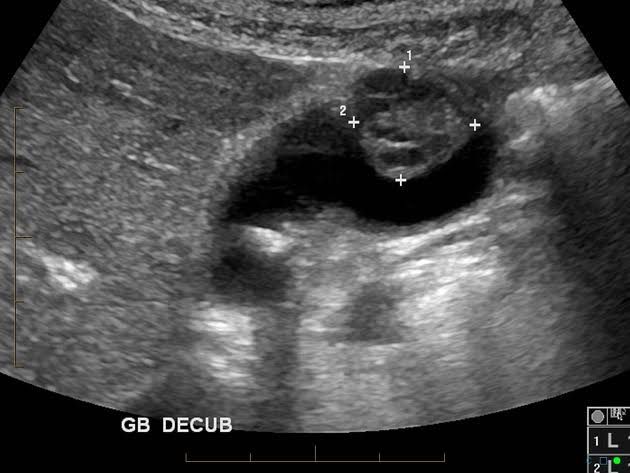

In gallbladder cancer, abnormal cells grow within the gallbladder. It's not known why this happens, but certain things are thought to increase your chances of developing the condition. Gallbladder cancer is more common in older people, and your chances of developing it increase with age. Lifestyle factors – such as obesity, smoking and an unhealthy diet – are believed to increase the risk of gallbladder cancer. However, there's not enough evidence to show a firm link between diet and gallbladder cancer. There are also a number of conditions that can increase your chances of developing gallbladder cancer. For example, gallstones, cholecystitis (inflammation of the gallbladder) and diabetes have been closely linked to the condition. If you have a family history of gallstones, cholecystitis, or gallbladder cancer, you're more likely to develop these conditions yourself.